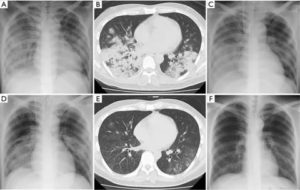

- Рентгенография грудной клетки – наиболее информативный способ выявление воспалительных процессов в легких (на снимках появляются характерные затемнения в местах поражения тканей и другие признаки заболевания);

- Фибробронхоскопия, КТ и МРТ грудной клетки необходимы тогда, когда поставить точный диагноз воспаление легких на основе вышеперечисленных методов по признакам невозможно.

Для постановки диагноза необходимо сделать рентгенограмму легких, а также сдать анализы крови и (при необходимости) мокроты. Кашель на ранних стадиях проявляется не у всех.